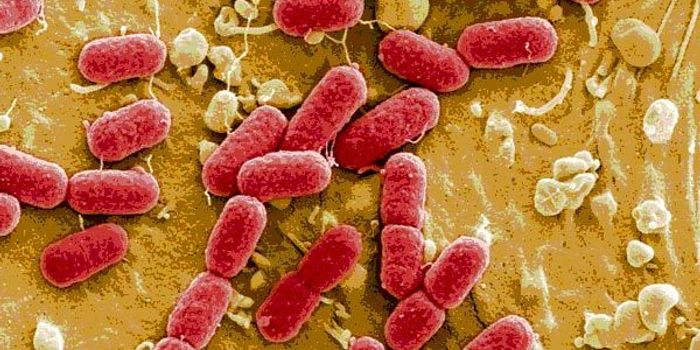

AUG 20, 2015MicrobiologyWhile most E. coli living in the intestine of people and animals are actually beneficial, some can cause severe illness. ...

AUG 13, 2015MicrobiologyEscherichia coli was first recognized as a possible foodborne pathogen in 1975 in a California hospital with a patient e ...